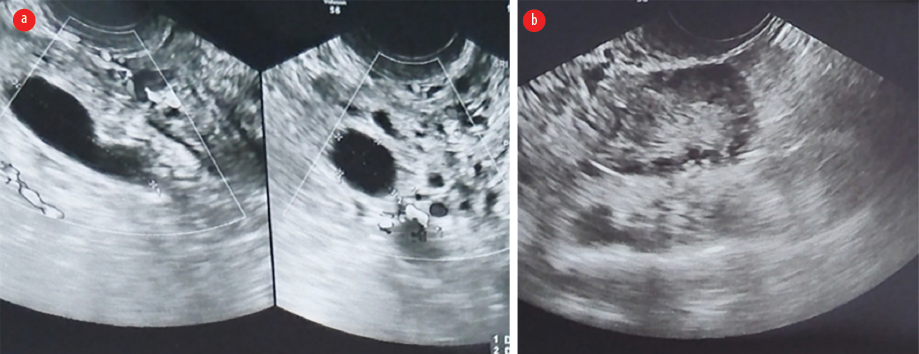

A 38-year-old female patient presented in the evening with severe lower abdominal pain since that morning. The patient had been treated with analgesics in an outside hospital, but the pain persisted. The patient had a history of two lower-segment cesarean sections and had undergone sterilization. Her last menstrual period was 15 days prior. On examination, the abdomen was normal except for tenderness in the left iliac fossa. Per speculum and per vaginal examination revealed tenderness in the left vaginal fornix with no other abnormalities. Serum beta-hCG < 0.100 mIU/mL, and the total count was 11 500 cells/mm3, with 85% neutrophils. The provisional clinical diagnosis was ovarian torsion or tubo-ovarian mass. Emergency US (USG) of the abdomen and pelvis showed a normal uterus with a normal endometrium and bilateral polycystic ovaries. An anechoic tubular structure (3.2 × 2.2 cm) with incomplete septation, suggestive of hydrosalpinx, was seen in the left adnexa, surrounded by a hyperechoic area with significant internal vascularity [Figure 1]. Arterial and venous flow were observed within the left pedicle. The diagnosis on USG was left hydrosalpinx with salpingitis or early phlegmon. A plain CT of the abdomen was advised to rule out any bowel pathology, but it did not provide additional insights into the diagnosis, except for a bulky left adnexa.

Figure 1: (a) Emergency ultrasound image showing tubular, anechoic, hydrosalpinx with surrounding increased echogenicity, heightened vascularity, and (b) polycystic right ovary with no features of torsion.

In our case, there were nonspecific findings of hydrosalpinx with increased adnexal echogenicity and a normal ovary. The heightened echogenic area may represent the torsed, inflamed tubal tissue on retrospective analysis. The right hydrosalpinx was obscured by bowel gas.